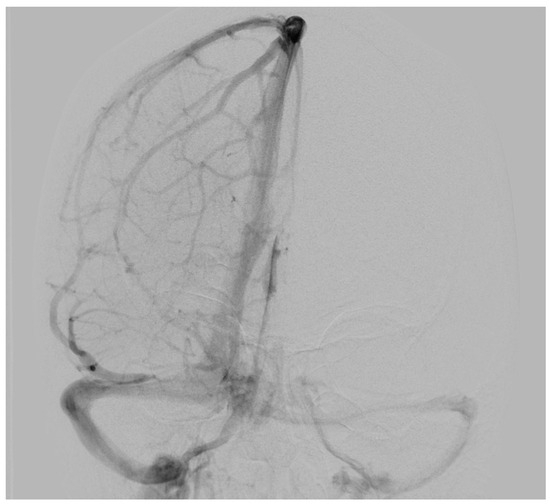

| Our first case | 34 | F | Extra-axial infratentorial on the right | Dizziness, headache, migraine (unrelated to venous hemangioma/no improvement of symptoms postoperatively) | No | 6 years | No recurrence at 3 months, No neurological deficits |